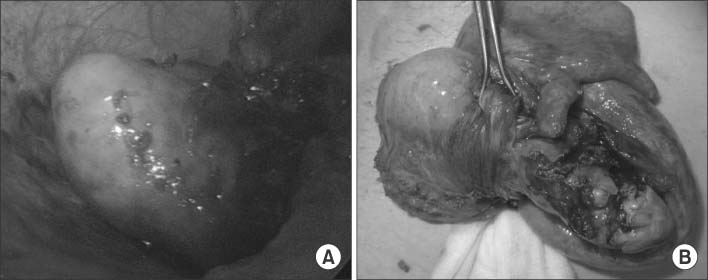

Operative findings showed a 3×3 cm appendiceal mass with dense severe adhesions (Fig. 2A, B) for which we performed an ileocecectomy.

Fig. 2

Intraoperative findings. (A) Laparoscopic appearance of appendiceal actinomycosis. (B) Gross appearance of appendiceal actinomycosis; a 7.0×4.0 cm appendiceal mass. Severe inflammation and adhesion between the appendix and the adjacent appendiceal serosal surface is visible.

Fig. 2 Intraoperative findings. (A) Laparoscopic appearance of appendiceal actinomycosis. (B) Gross appearance of appendiceal actinomycosis; a 7.0×4.0 cm appendiceal mass. Severe inflammation and adhesion between the appendix and the adjacent appendiceal serosal surface is visible.